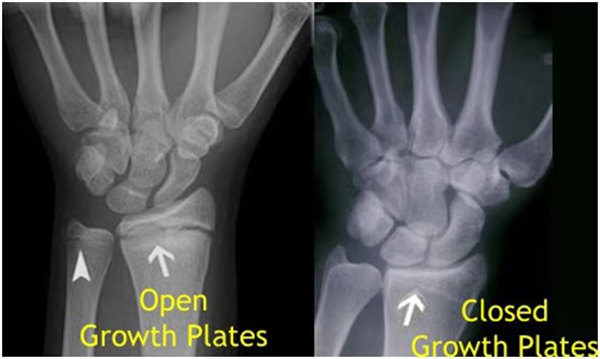

我們都知道,人體的高矮是由骨骼的生長發(fā)育決定的,特別是下肢長骨。長骨呈長管狀,在長骨的兩端有一種專管骨骼生長的骺軟骨,它與干骺端之間有一盤狀軟骨結構稱為骺板(線),在幼兒的X光片上表現(xiàn)為一條較寬的透光帶。 (見下圖)

未成年時隨著年齡的增加骺軟骨端不斷骨化,骨骼就不斷增長。當骨骺線完全閉合時骨骼就停止生長,個子也就不再增長了。一般骨骺端完全閉合的年齡是18~20歲左右。